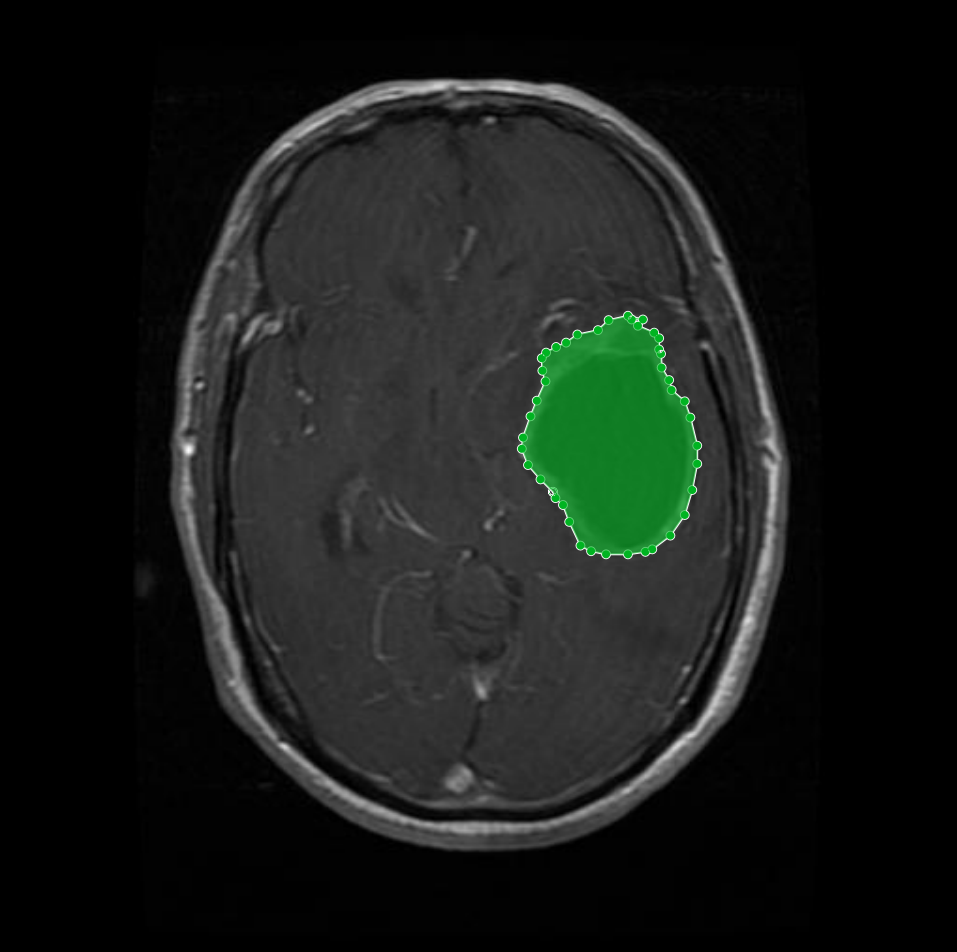

Figure 7: Samples of partial-region underannotations. The purple area indicates regions that were initially marked as non-tumorous but were later identified by the radiologist and physician as tumorous.

Conversely, there were cases where genuine tumor regions had been overlooked during the initial annotation process. With input from the Physician and radiologist, these missing regions were added to the annotations, ensuring that the masks comprehensively captured all tumor areas. Figure 7 demonstrates an example of such an adjustment, where previously unannotated tumor segments were correctly incorporated into the final mask.